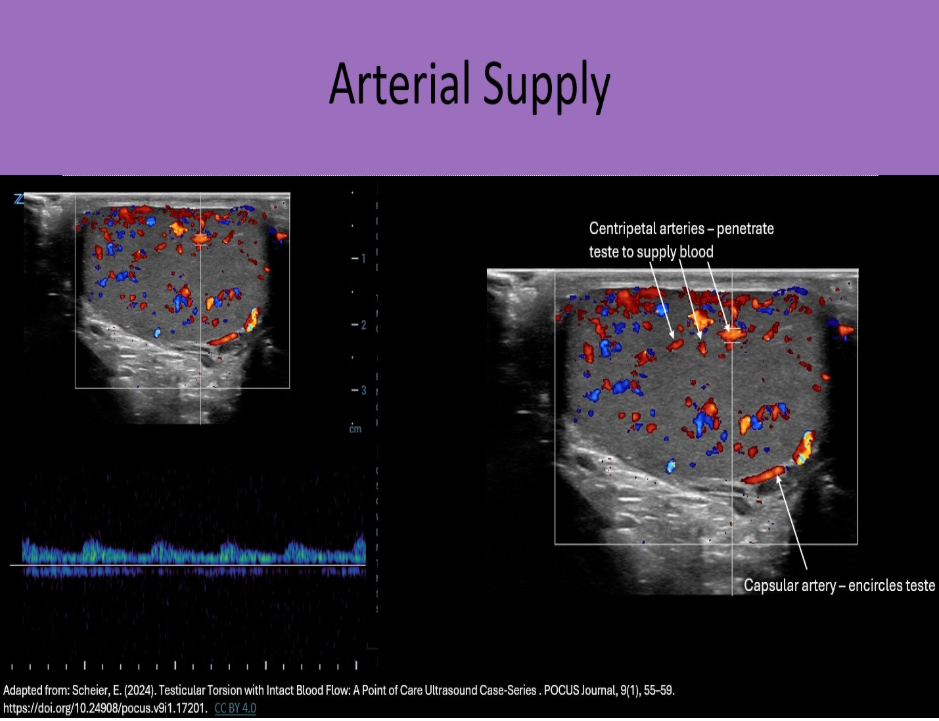

When evaluating intratesticular flow, which vessel is sampled by Doppler?

D. centripetal

Centripetal arteries course through the parenchyma to deliver oxygenated blood to the testicular tissues. These arteries are sampled with Doppler in a standard ultrasound evaluation.

Which scrotal artery supplies the epididymis?

B. deferential

Capsular artery courses along the testicle periphery and produces branches called centripetal arteries which course through the parenchyma. The deferential artery supplies vas deferens and epididymis with blood. The cremasteric artery supplies scrotal sac with blood.

Which scrotal arteries penetrate the testicular parenchyma to supply oxygenated blood?

A. centripetal

Which scrotal artery encircles the testicular periphery?

B. capsular